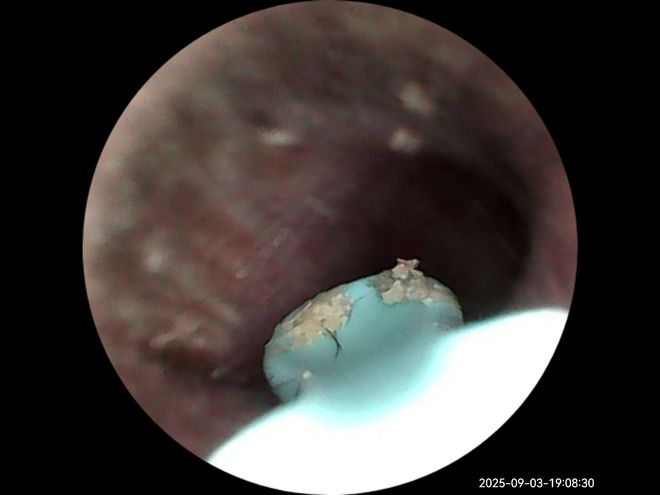

提到可视化,说下西圣Find X跟杂牌耳勺的区别,也是选它的第二大原因。西圣Find X采用1500W像素的内窥镜, 同时有多层光学镀膜镜组,成像清晰、透光率高、色彩还原度高。另外西圣自研了A-Zoom2.0动态调焦系统,说人话就是你掏耳朵即便手再抖,成像都是清晰的,不会糊掉,看得清,清理起来也放心。

最后,搭配专门的App,你还能在掏耳朵的同时录像、拍照,时刻能记录耳道状况。耳朵不舒服时,直接探进耳道查看一下,发炎、耳膜破裂、耳结石等等一看便知。